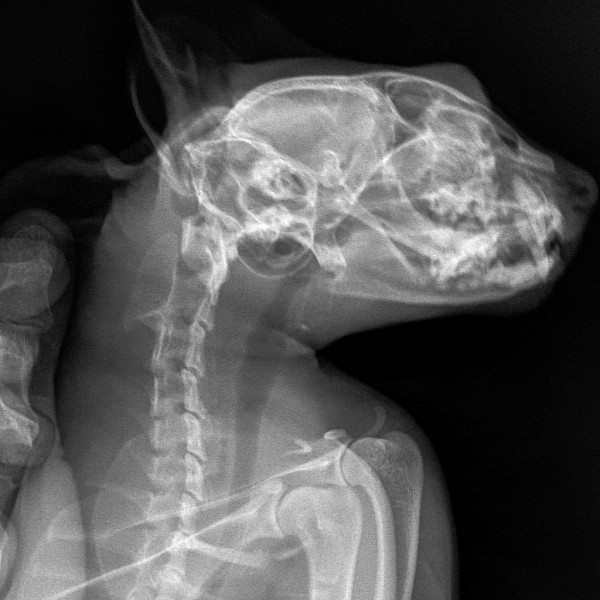

Сделали 3 рентгеновских снимка:

http://www.imageup.ru/img14/3262899/2019-01-18-pestrushka-03.jpg

На снимке головного мозга кошки врач предположительно нашёл небольшие тёмные пятна справа (???), и сказал, что это расширенные сосуды по типу варикоза и они давят на мозг, в результате чего животное бьётся в судорогах. Но это неточно и нужны консультация ветеринара-невропатолога и МРТ головного мозга кошки.